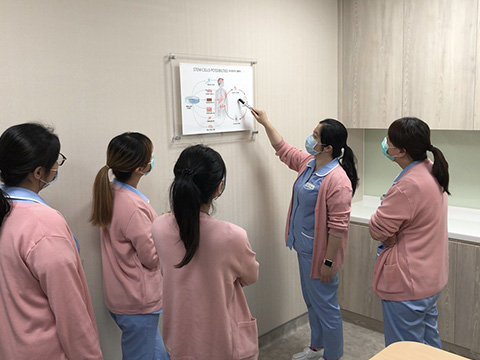

Astrid Clinic is committed to providing personalized consultation and comprehensive treatment options with a specialist medical team from Imperial College London School of Medicine, Imperial College London, Philipps-Universität Marburg (Germany) School of Medicine, National Taiwan University Hospital, and Kaohsiung Medical University. Next-generation sequencing (NGS) and drug sensitivity test of circulating tumor cells aim to determine an optimal therapy for each individual patient.

We now have more than 30 medical researchers, including scientists with Ph.D. and Master’s degrees in various biomedical fields, engaging in studies of tumor immunotherapy, intra-arterial chemotherapy, cancer genomics analyses, cancer-antigen targeted therapies and genetic engineering techniques for highly individualized precision medicine.

In addition to the operation room, observation room and recovery room for professional surgical services, the Astrid Clinic also provides patients and their families with warm and comfortable environments for their stay, such as separate, quiet and comfortable areas for waiting, for consultation, for out-patient chemotherapy, for minor surgical procedures, etc., in order to provide the warmest reception and care, and also to protect the privacy.